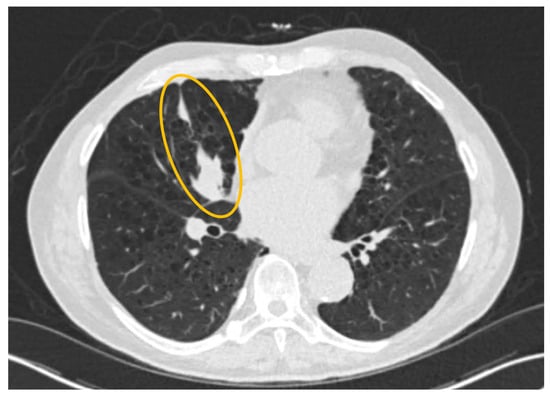

Not All PET-Avid Endobronchial Lesions Are Malignant: A Case of Chronic Foreign Body Aspiration

Background: Low-dose CT scanning is a key tool in lung cancer screening, enabling the detection of clinically significant abnormalities in asymptomatic individuals and often prompting further diagnostic evaluation. Case Presentation: We describe the case of an 80-year-old man with a heavy smoking history [...] Read more.

Background: Low-dose CT scanning is a key tool in lung cancer screening, enabling the detection of clinically significant abnormalities in asymptomatic individuals and often prompting further diagnostic evaluation. Case Presentation: We describe the case of an 80-year-old man with a heavy smoking history who was found to have a new right middle lobe collapse on screening CT. Subsequent positron emission tomography-computed tomography (PET/CT) imaging demonstrated mild fluorodeoxyglucose (FDG) uptake (SUVmax 2.7), raising concern for a low-grade endobronchial malignancy versus mucoid impaction. Flexible fiberoptic bronchoscopy revealed a large exophytic endobronchial mass occluding the airway. Histopathologic examination of the biopsy sample unexpectedly revealed vegetable material, consistent with chronic foreign-body aspiration. Discussion: Unrecognized aspiration events are relatively common in elderly adults and can mimic malignancy on imaging. This case highlights an important diagnostic pitfall: inflammatory endobronchial processes, including foreign-body granulomas, can demonstrate FDG uptake and mimic malignancy. Conclusion: Clinicians should maintain a broad differential diagnosis when evaluating PET-avid endobronchial lesions, especially in elderly patients. Full article

Show Figures

Figure 1